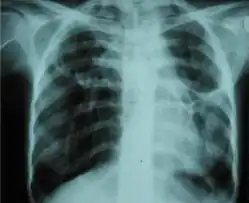

A fibrothorax can typically be diagnosed by taking an appropriate medical history in combination with the use of appropriate imaging techniques such as a plain chest X-ray or CT scan.[3] These imaging techniques can detect fibrothorax and pleural thickening that surround the lungs.[7] The presence of a thickened peel with or without calcification are common features of fibrothorax when imaged.[3] CT scans can more readily differentiate whether pleural thickening is due to extra fat deposition or true pleural thickening than X-rays.[3]

If a fibrothorax is severe, the thickening may restrict the lung on the affected side causing a loss of lung volume.[7] Additionally, the mediastinum may be physically shifted toward the affected side.[3] A reduction in the size of one side of the chest (hemithorax) on an X-ray or CT scan of the chest suggests chronic scarring.[6] Signs of the underlying disease causing the fibrothorax are also occasionally seen on the X-ray.[6] A CT scan may show features similar to those seen on a plain X-ray.[7] Lung function testing typically demonstrates findings consistent with restrictive lung disease.[6]

Chest radiograph displaying inhomogeneous opacification of the left half of the chest that is fibrothorax -